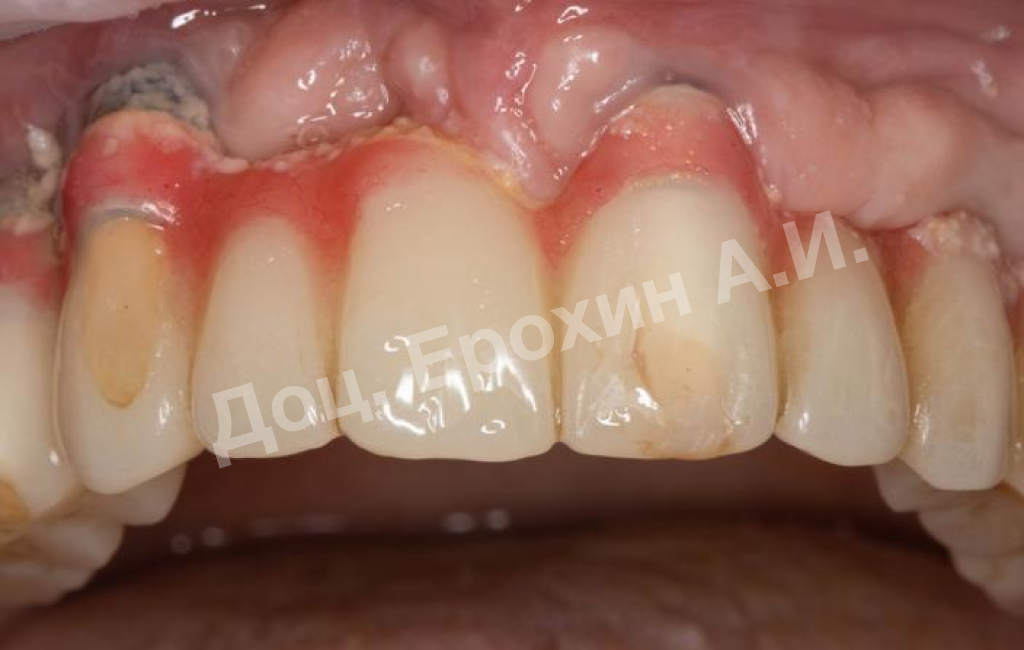

Более 10 лет назад пациентке была проведена тотальная имплантация с полным протезированием. В области имплантатов 22–24 была проведена пересадка эпителиального трансплантата с целью создания зоны кератизированной прикрепленной десны. После проведения данной операции пациентка по личным причинам не захотела заниматься мягкими тканями и пропала на 10 лет.

В результате, спустя 10 лет мы видим, что единственная часть десны в области имплантации, не затронутая рецессиями, — это зона, где была проведена трансплантация десневого фрагмента. С целью стабилизации имеющихся имплантатов на повторном приеме была проведена вестибулопластика по Кларку с фиксацией мягкотканных мукотомов, фрагментов эпителия с неба, зафиксированных швами.